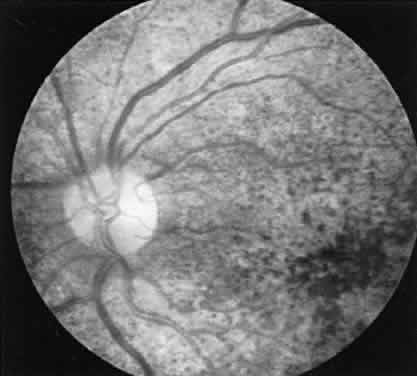

CASE 3 (FIG. 10). A 57-year-old female was referred because of increasing complaints of difficulty with her night vision and her side vision. She had a long history of low-grade uveitis and a progressive decrease in central vision. Visual acuity 20/100 OD, 20/80 OS. The vitreous showed multiple small cells. Both retinas showed narrowed arterioles and strands of pigment in the far periphery. Multiple areas of atrophy of the RPE were seen throughout. An ERG was extinguished.

Fig. 10. Case 3. Left. Posterior pole. Right. Peripheral retina. See text for details.

This patient had birdshot choroiditis, an inflammatory disorder of the choroid with severe secondary photoreceptor degeneration. The ERG gives evidence of widespread degeneration, but the history and clinical findings preclude the diagnosis of a generalized heredoretinal degeneration. This disorder of birdshot choroiditis may produce a “pseudo-retinitis pigmentosa” picture8 (Table 2).